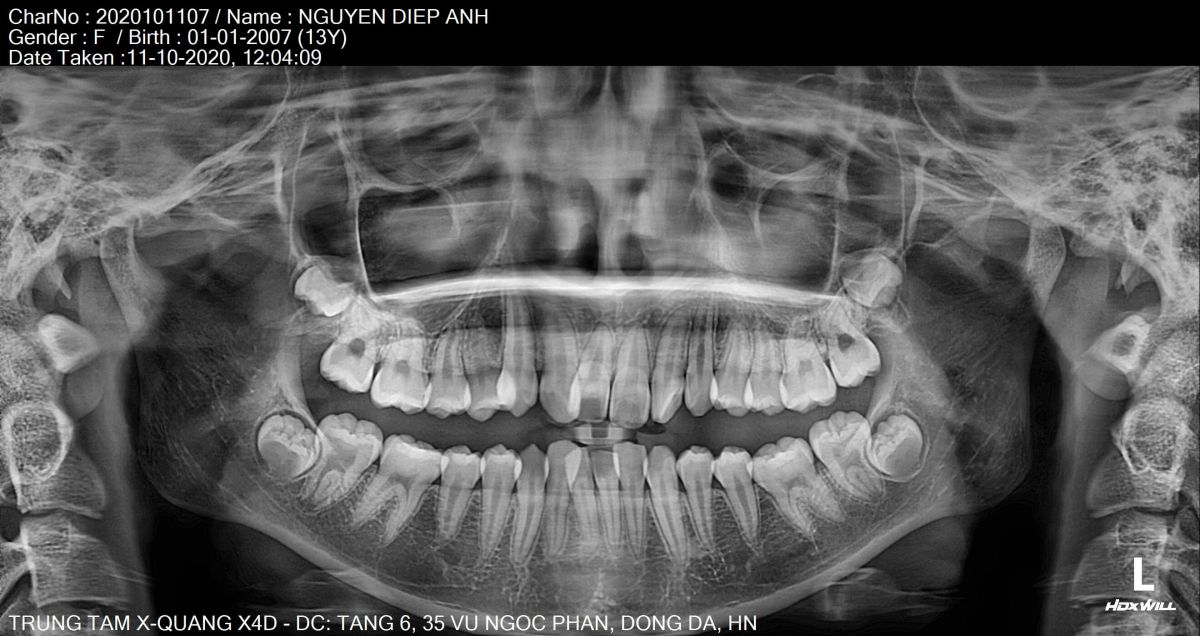

Lập kế hoạch điều trị khoa học với công nghệ độc quyền BIOSMART

Tại Hanseoul, Diệp Anh được điều trị bằng công nghệ niềng răng Biosmart – giải pháp chỉnh nha thế hệ mới với nhiều ưu điểm vượt trội:- Tối ưu lực kéo, nhẹ nhàng nhưng hiệu quả gấp 4 lần

- Di chuyển răng chính xác, an toàn nhờ phần mềm lập kế hoạch 3D

Bác sĩ chỉnh nha chuyên sâu trực tiếp xây dựng phác đồ dựa trên phim X-quang, hình ảnh 3D và phân tích khớp cắn, đảm bảo răng di chuyển đúng hướng – đúng lực – đúng thời điểm.